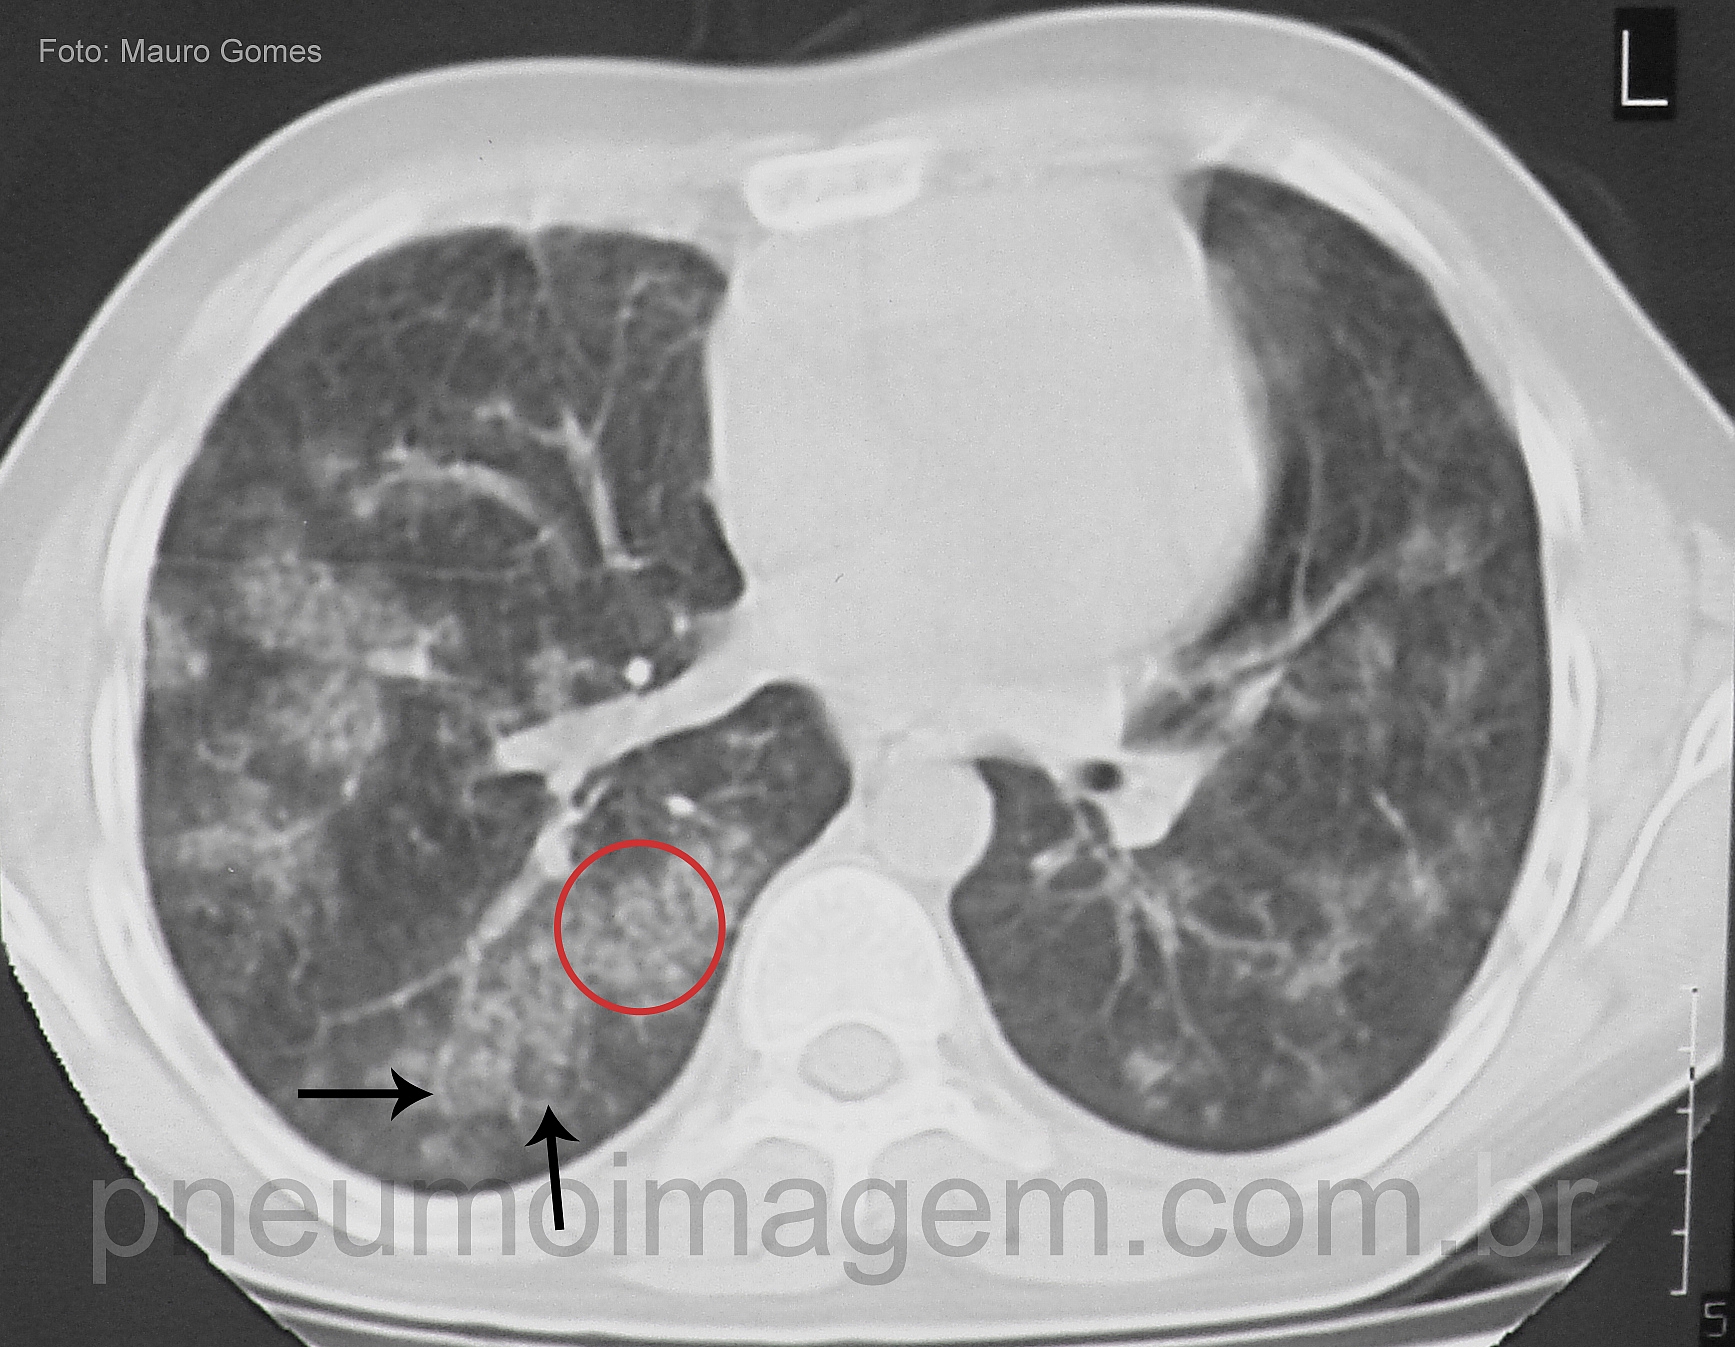

DESTAQUES DO ERS2016: HEMORRAGIA ALVEOLAR DIFUSA (HAD)A HAD é uma doença rara, mas muito grave. Os achados típicos à TC de tórax são opacidades bilaterais e difusas em vidro fosco, frequentemente dos ápices até os ângulos costofrênicos. A terça parte dos pacientes não tem hemoptise à apresentação inicial da doença.